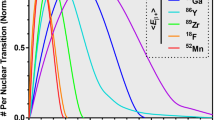

The large differences in image blur due to the positron flight in human compact bone, soft tissue and lung tissue from some characteristic positron point sources are illustrated in Fig. 1. The corresponding one-dimensional annihilation probability distribution functions \( {aPSF({}_{z}X^{A} ,T_{i} ,x)} \), as a function of distance from the point source, are presented in Fig. 2 for each radionuclide and for each of the selected tissues. All projected distributions of annihilation events were cusp shaped around the positron point source. Due to this characteristic shape, all related FWHM values were well within the system resolution of a modern PET camera (4–5 mm). The corresponding \( {FWTM(T_{{j,}} {}_{Z}X^{A} )_{{aPSF}} } \) values, on the other hand, varied from 0.65 mm in bone up to 2.7 mm in lung tissue for 18F and from 4.5 mm in bone up to 20.3 mm in lung tissue for 82Rb. This is illustrated in Table 1 together with the values at the 20% level, \( {FW20M(T_{{j,}} {}_{Z}X^{A} )_{{aPSF}} } \).

The properties of the positron annihilation distributions are further illustrated in Table 2, which shows the fraction of events within the selected widths of \( {aPSF({}_{z}X^{A} ,T_{i} ,x)} \). The fractions decrease with decreasing tissue density and increasing positron energy. This may be due to the different energy-dependent scatter properties of the considered media and their influence on the positron transport mechanisms. Furthermore, the fractions obtained within the selected levels of Table 2 are in clear contrast to those obtained for a standardised Gaussian distribution, normally taken as an estimator of the system spatial resolution, where the corresponding constant fractions for the FWHM and the FWTM are respectively 76% and 97%.

The impact of the positron distance of flight on total spatial resolution is illustrated in Fig. 3 as a function of the system spatial resolution. These curves show the positron annihilation point spread distribution convolved with Gaussian functions, representing various spatial resolution of the PET camera. The disturbing image blur caused by the positron flight becomes increasingly important when aiming at high-resolution PET cameras, with a system spatial resolution below 5 mm FWHM. The higher the system spatial resolution, the higher is the contribution of the positron flight to the loss of spatial resolution in the image plane. In a PET camera with 3 mm system resolution, for instance, the loss of spatial resolution due to the positron distance of flight accounts for 1.3% in bone and 3.5% in soft tissue but up to 22.5% in lung tissue for 18F. The corresponding values were, respectively, 2.9%, 9.3% and 45.0% for 11C and 37.9%, 68.9% and 167% for 82Rb.

The results obtained by estimating the total PET spatial resolution using the root mean square method of Eq. 3 are presented in Table 3. Also indicated are the deviations from the FWHM values obtained after direct convolution, \( {FWHM(T_{{j,}} {}_{Z}X^{A} )_{{Convolved}} } \). From these results, it is shown that the measure of the width at the 20% amplitude level, FW20M, seems to be a more representative measure than FWHM in estimations of the spatial resolution losses due to the positron flight in PET.

The average range or the FWHM of the positron flight distribution in water has been commonly used as a measure of the spatial resolution losses due to the positron flight distribution in PET. However, as indicated by the results of this work, the projected distribution of annihilation origins around a point source has a shape that differs from a Gaussian distribution. Hence, the conventional measures like FWHM or FWTM of the positron distribution do not accurately predict the spatial resolution losses in PET. Furthermore, a much lower fraction of events are present within the conventional limits for the positron annihilation distribution than for a corresponding Gaussian function. The long tails of the obtained annihilation probability distributions around the positron source are likely to contribute to the image blur with low-frequency components, mixed with those of the scatter distribution. This has to be carefully considered when selecting a single width parameter for estimating the resolution losses according to Eq.3. The full width at twentieth maximum measure, \( {FW20M(T_{{j,}} {}_{Z}X^{A} )_{{aPSF}} } \), was found to produce values that were relatively close to those obtained by convolving the annihilation distribution function with the (Gaussian) system resolution function for compact bone, soft tissue and adipose tissue. For lung tissue, the differences remained fairly large and displayed a tendency to increase with increasing positron emission energy.